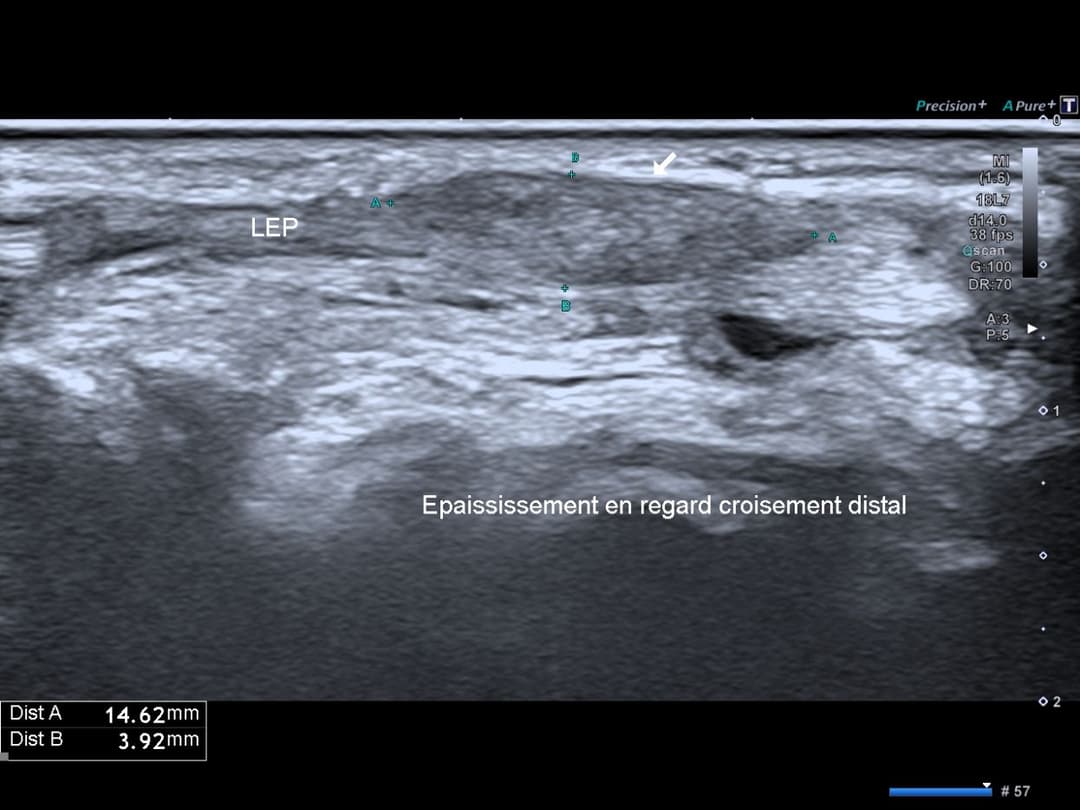

Désorganisation architecturale du tendon EPL au niveau du croisement avec le compartiments des extenseurs radiaux, qui présentent un épanchement dans leur gaine synoviale.

Coupe sagittale au niveau du croisement distal, épaississement fusiforme du tendon avec désorganisation architecturale